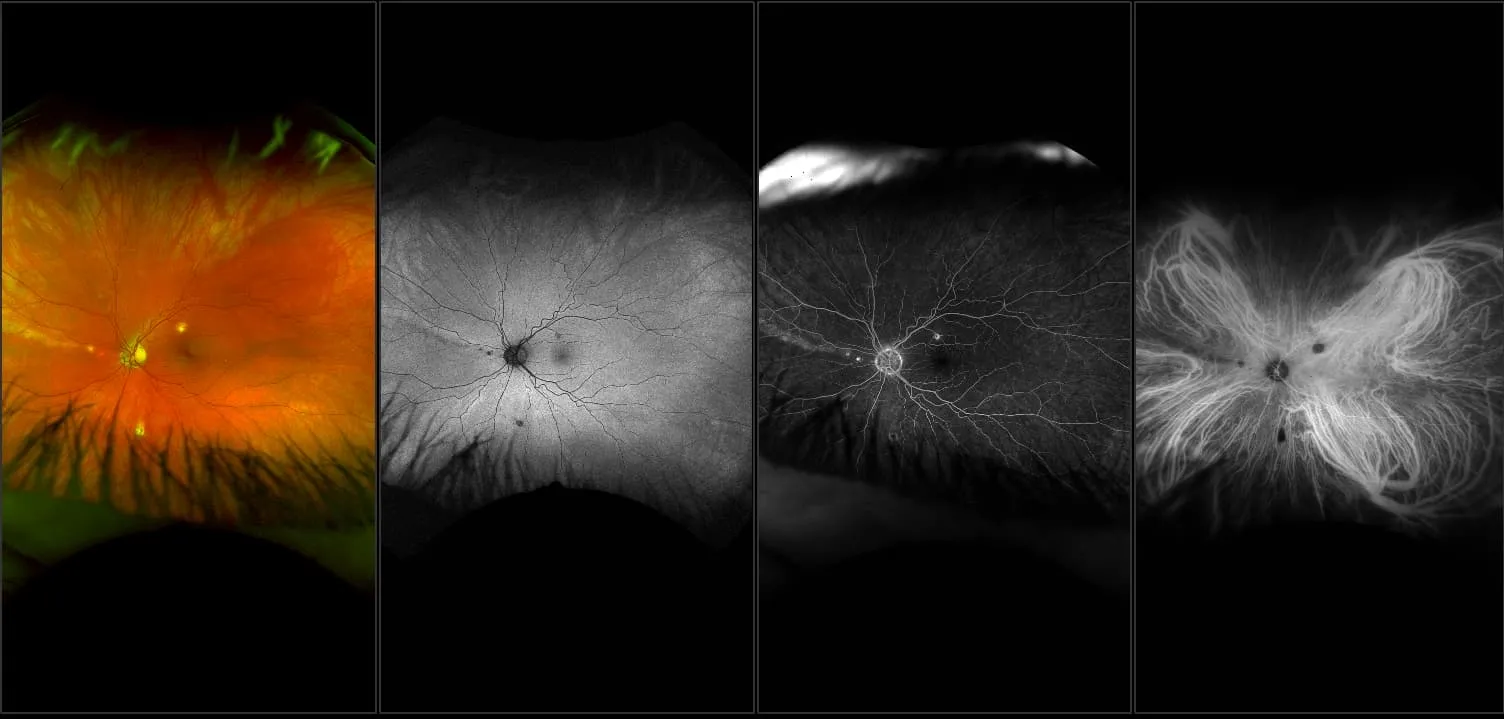

MonacoPro - Vitreous Floaters, RG, OCT

Vitreous floaters are microscopic collagen fibers within the vitreous that tend to clump and cast shadows on the retina, appearing as floaters to the patient.